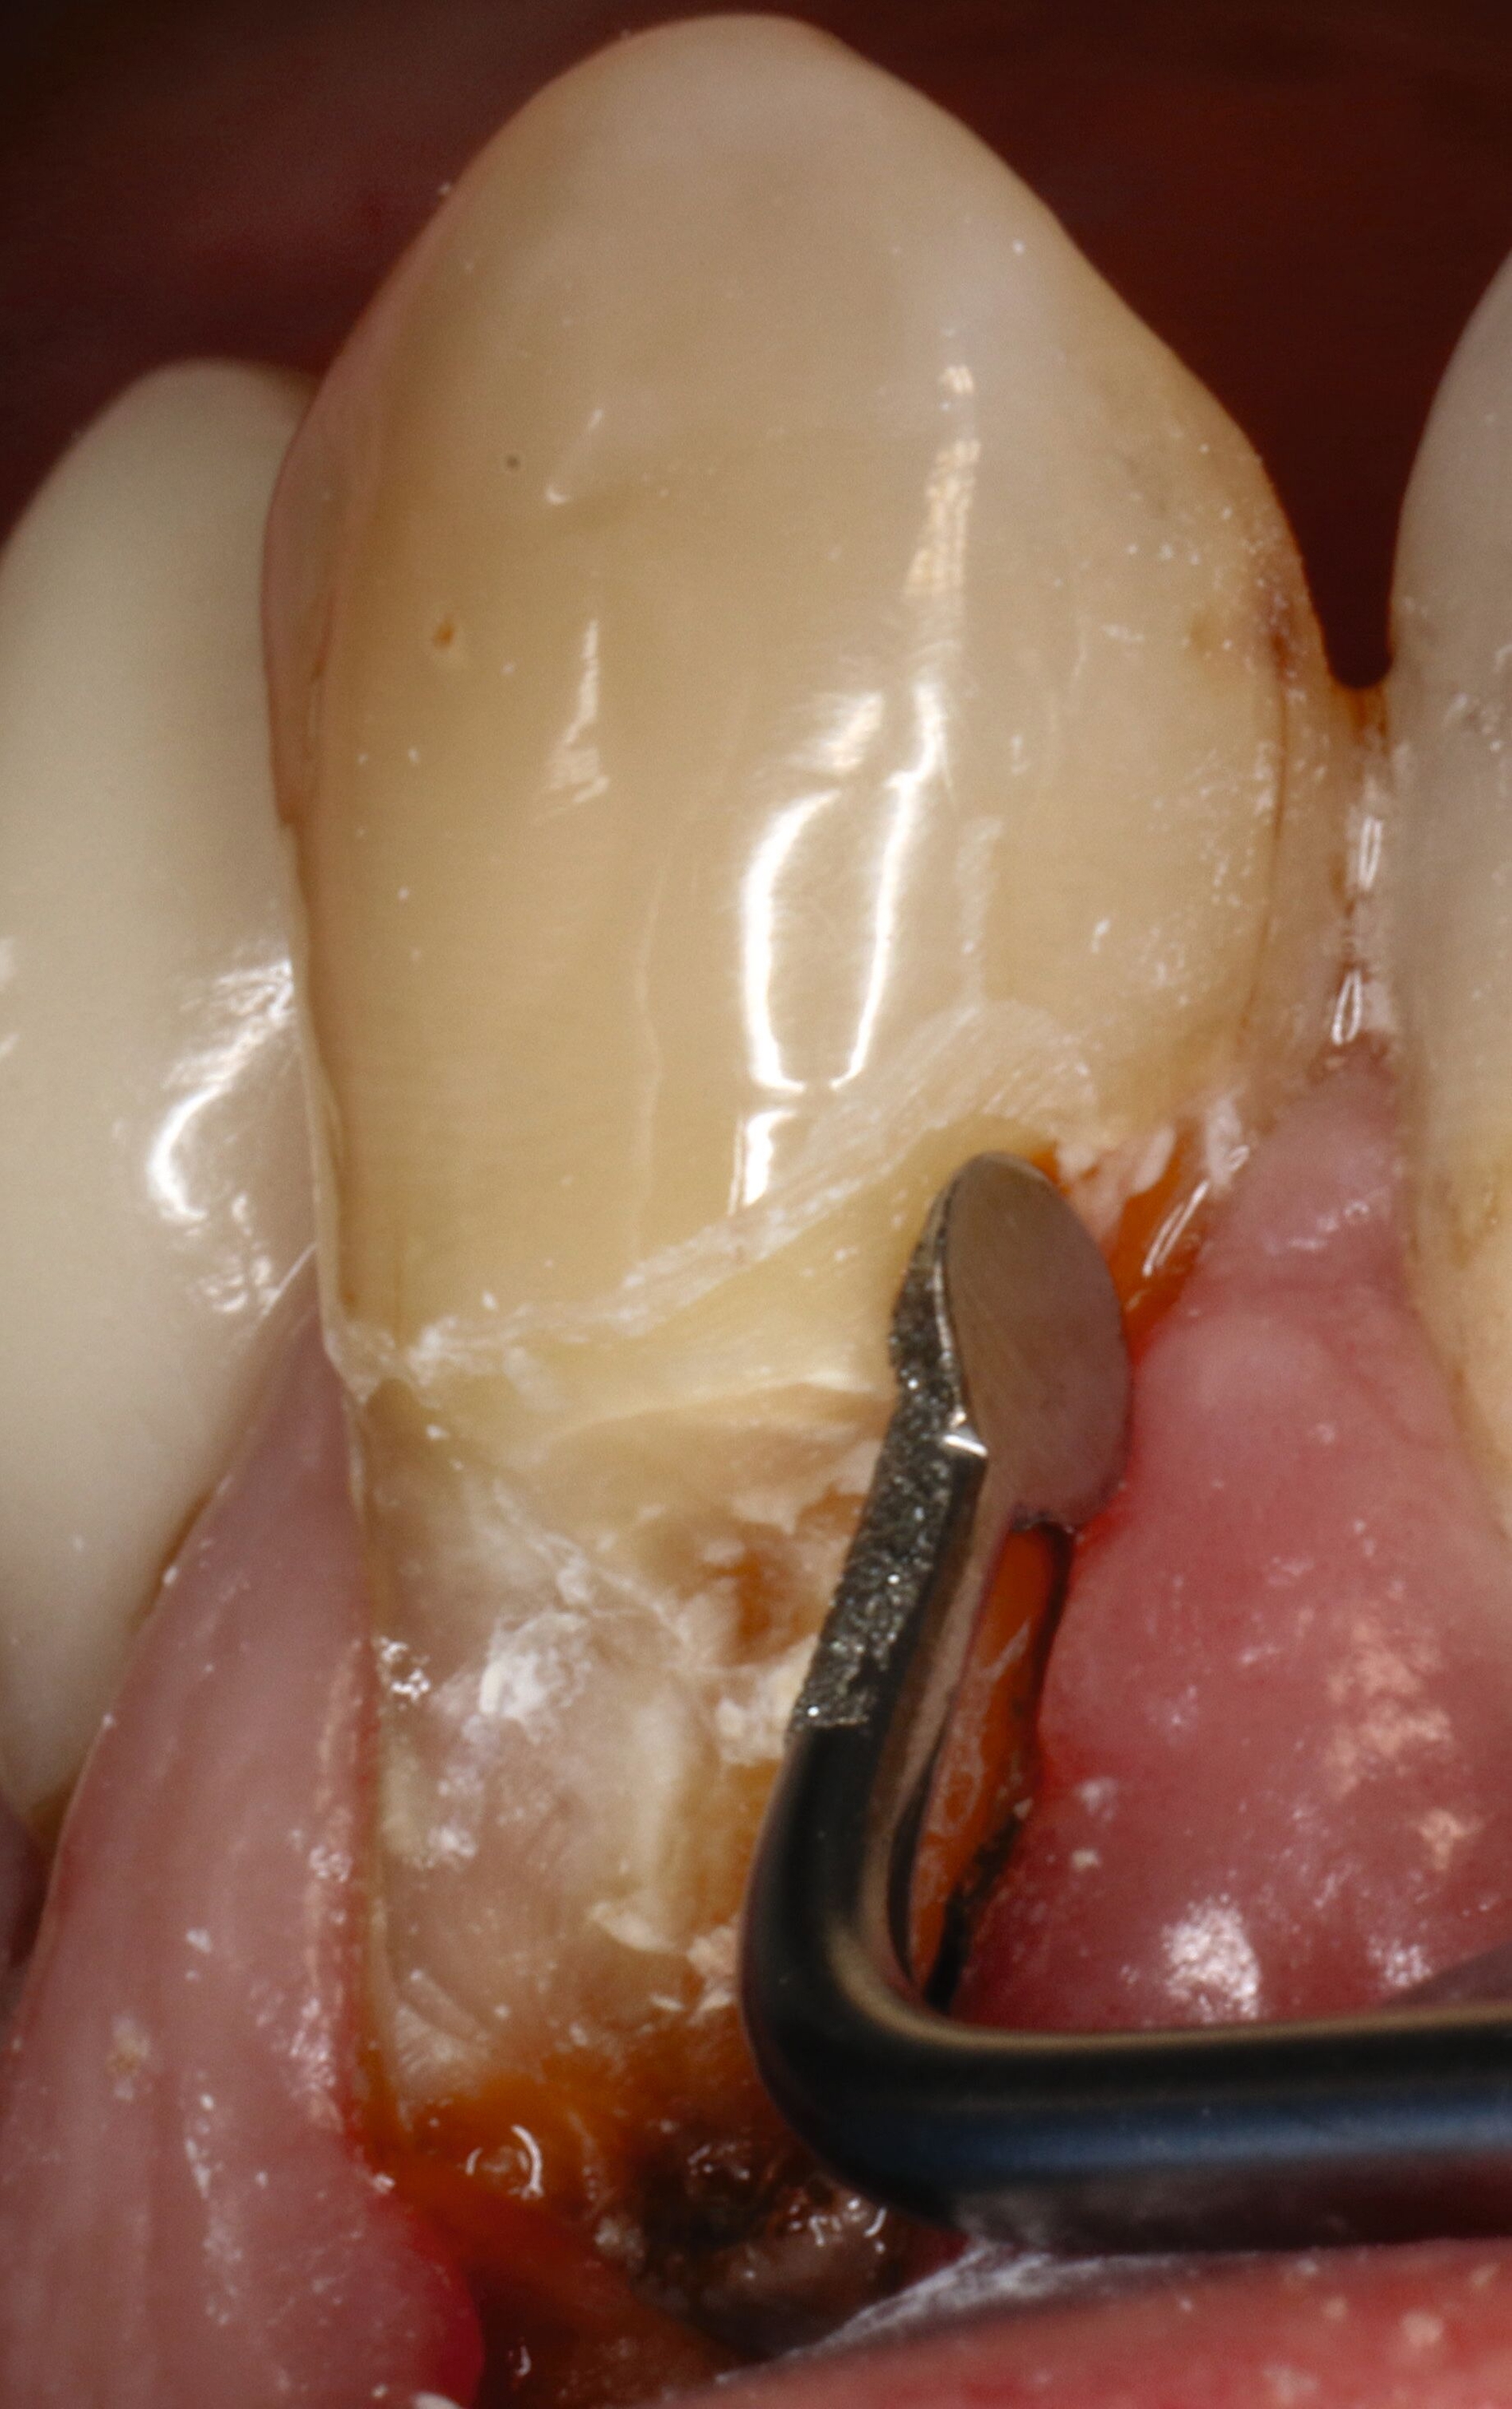

Abbildung 8 beschreibt einen Behandlungsablauf bei einer präexistenten Restauration an Zahn 23 mit deutlich sichtbarer Sekundärkaries zervikal und approximal (Abbildung 8a). Nach der Entfernung der alten Restauration (acht Jahre) zeigt sich das ganze schwer zu restaurierende Ausmaß des Defekts (Abbildung 8b).

Auf den ersten Blick ist klar, dass eine effektive Matrizentechnik hier schwierig wird, dass aber freies Schichten aufgrund der Nähe zur Gingiva ebenfalls keine gute Idee darstellt. Zur Kariesexkavation favorisieren wir schallschwingende, einseitig belegte Instrumente, die in der Regel keine Blutung provozieren, selbst wenn sie subgingival eingesetzt werden (Abbildungen 8c und 8d).